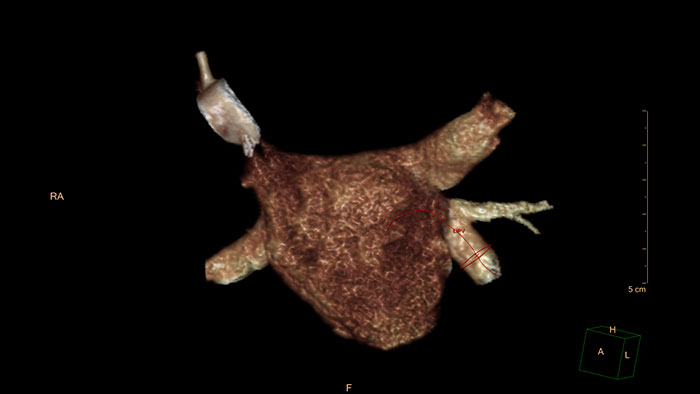

CT EP Planning

EP procedures planning

CT EP Planning allows electrophysiologists to quickly identify anatomy relevant to the EP procedure.

Benefits

- Provides, overall assessment of pulmonary veins, left atrial, and appendage anatomy, enabling the electrophysiologist to identify anatomy that may complicate the EP procedure.